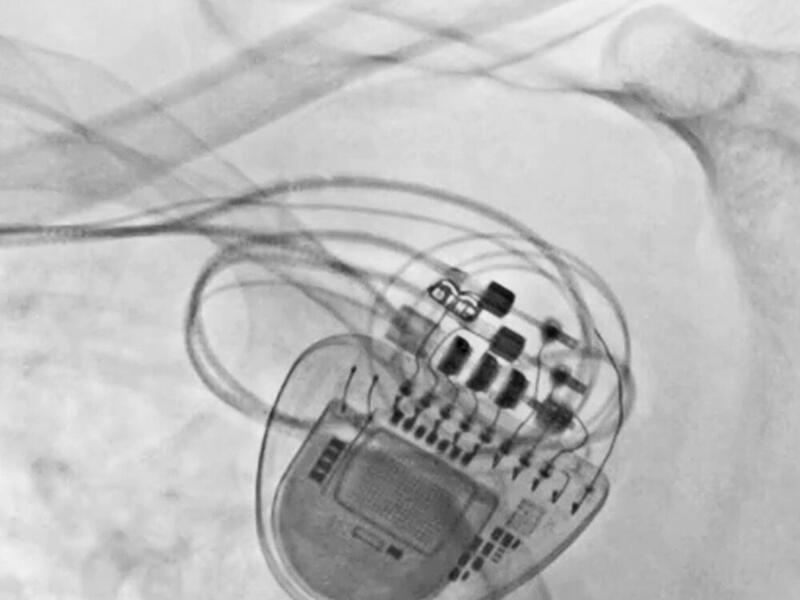

Der Kulmbacher Ehrenbürger hat demnach einen hochmodernen CRT-P-Herzschrittmacher bekommen. Dieser ist nicht ganz einfach einzusetzen. Nach nur wenigen Tagen war der Bezirkstagspräsident schon wieder einigermaßen fit und konnte vor allem mit seiner Familie ohne bange Gefühle die Feiertage genießen.

Aufgrund der Vorgeschichte der Herzerkrankungen des Kulmbacher Altoberbürgermeisters habe es ein „einfacher“ Schrittmacher nicht mehr getan. „In so einem Fall brauchen die Patienten ein System, das sowohl die rechte als auch die linke Herzkammer stimuliert. So ein Dreikammersystem ist allerdings deutlich aufwendiger als ein normaler Schrittmacher.“

Bis zu 300 Schrittmachersysteme im Jahr werden laut Dr. Brugger pro Jahr in Kulmbach am Klinikum implantiert. Zwischen 15 und 20 Prozent seien sogenannte biventrikuläre Systeme. Die seien deutlich vorteilhafter, wenn es darum geht, die Pumpleistung des Herzens zu sichern und immer mehr auf dem Vormarsch, auch wenn der Einbau deutlich aufwendiger sei als der eines einfachen Schrittmachers.

„Vom CRT-P Herzschrittmacher gehen drei Elektroden weg, die im rechten Ventrikel, im rechten Vorhof und in einer Herzvene an der betroffenen Herzkammer platziert werden müssen“, ergänzt Dr. Brugger und erklärt, dass speziell das Platzieren der Elektrode in der Herzvene an der Kammer schwierig sei.

Ein kleiner Zugang in der Wand des rechten Vorhofs müsse dafür lokalisiert werden, um die Elektrode genau zur Herzkammer vorzuschieben. Nur so könne der gestörte Signalweg überbrückt werden, damit das Herz wieder synchron schlägt.